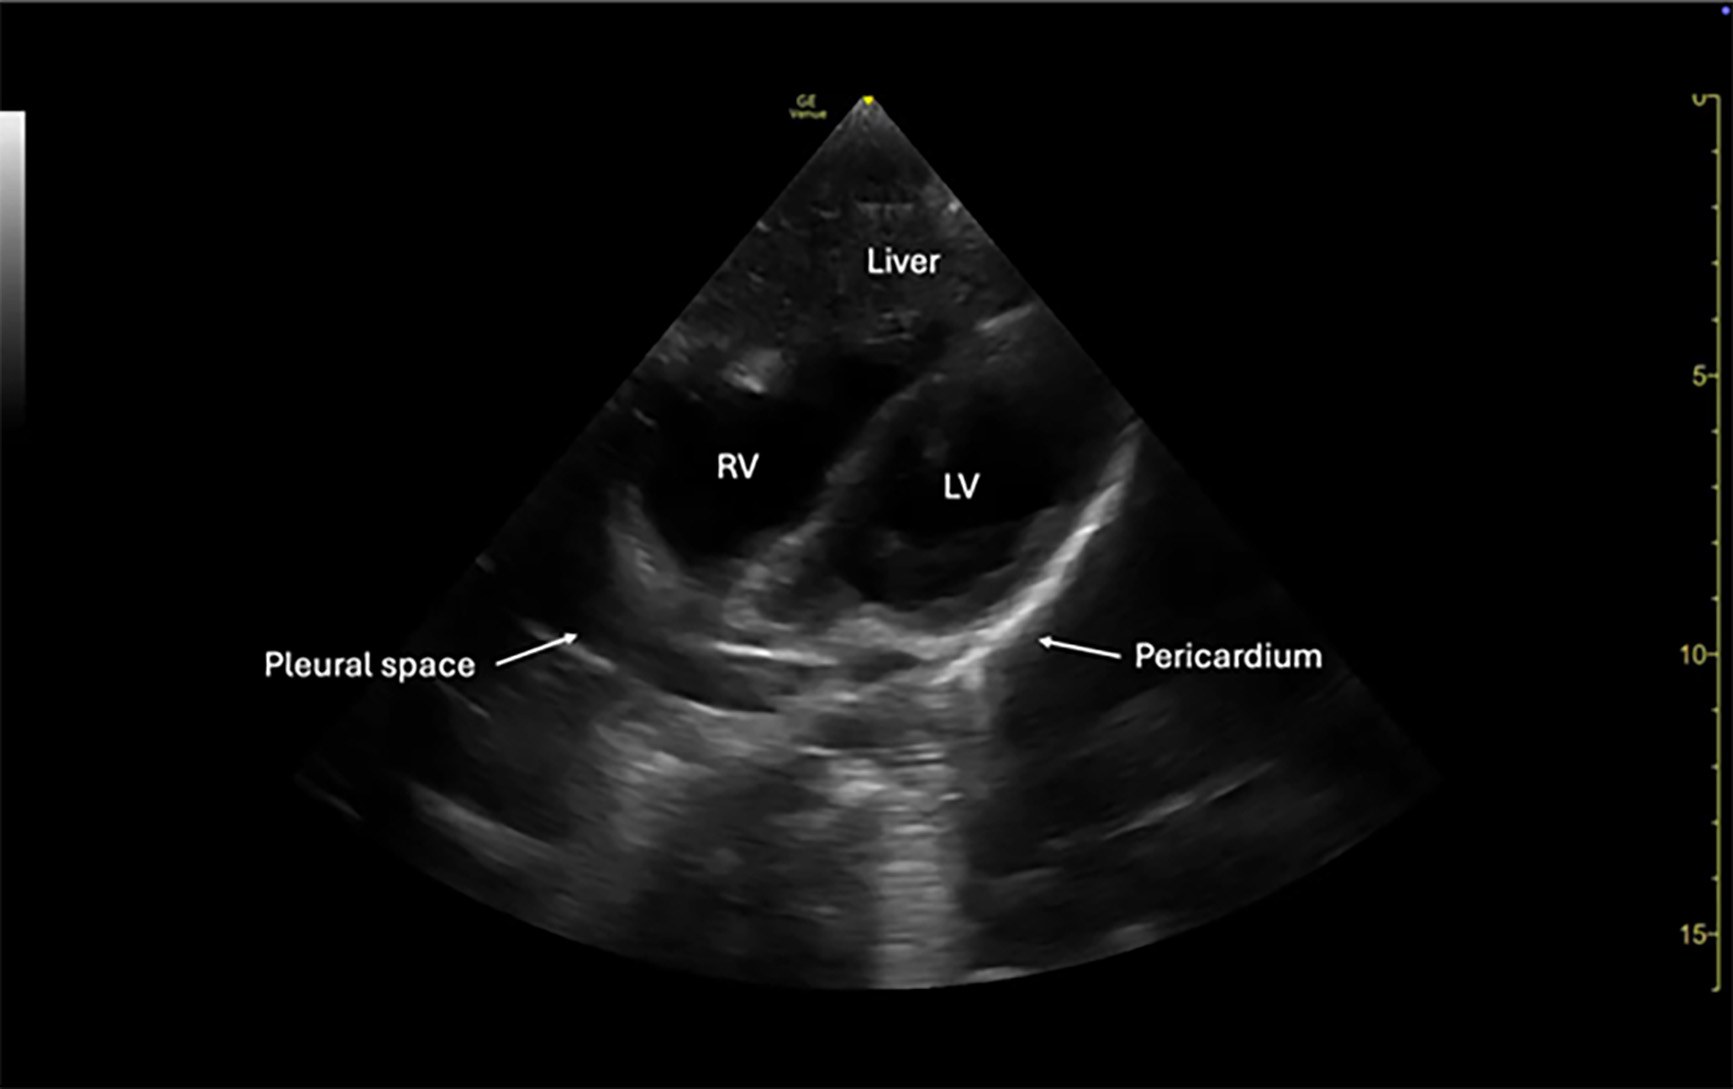

Subxiphoid

The subxiphoid (also called subcostal) view in pediatric trauma can be obtained in one of two ways. One is by placing the phased array or curvilinear probe directly over the epigastric area and angling superiorly toward the left shoulder beneath the rib cage, and the other is by placing the probe directly on the anterior chest wall, especially when abdominal tenderness or guarding precludes the subcostal approach. The choice of technique is influenced by patient body habitus, injury pattern, and comfort. In smaller children or infants, subxiphoid imaging often is more successful because of relatively compliant abdominal walls and less rib ossification.31

This view is used primarily to assess for pericardial effusion, which may indicate cardiac injury or tamponade physiology in the setting of blunt or penetrating trauma. The goal is to obtain a complete four-chamber view of the heart to evaluate for anechoic fluid surrounding the myocardium, typically appearing between the posterior pericardium and right ventricle.38 It also is helpful for assessing right ventricular collapse, chamber compression, or a “swinging heart” in cases of tamponade.

A pericardial effusion causing tamponade physiology is rare but life-threatening and its detection is a critical component of the FAST exam. Focused cardiac ultrasound has a sensitivity of about 96% and specificity of 98% to 100% for detecting pericardial effusion, although these values may vary depending on the clinician.40 Early identification of pericardial blood can prompt rapid intervention, such as pericardiocentesis or surgical exploration.41

Probe orientation is variable since the main focus is identification of a pericardial effusion. ATLS teaches that the probe marker is directed to the patient’s right, while the majority of cardiac windows are obtained with the marker directed toward the patient’s left. Regardless, a generous amount of gel should be used to improve image acquisition through abdominal structures such as the liver. In uncooperative or unstable patients, image acquisition may be limited; however, even partial visualization of the pericardial space can be diagnostically useful. (See Figure 3.)

Figure 3. Normal FAST Subxiphoid View |

5-year-old female via phased array probe |

FAST: Focused Assessment with Sonography for Trauma Image courtesy of: Matthew D. Holmes, MD. |